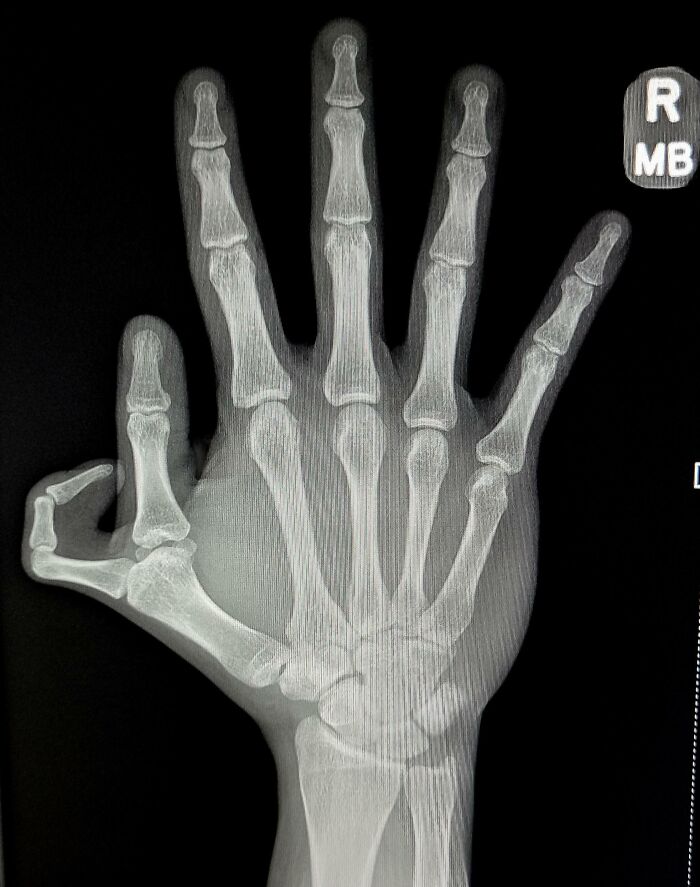

Tengo 7 muelas del juicio

Si lo pasamos mal cuando nos salen las muelas del juicio, no me imagino esta pobre persona, con nada menos que siete